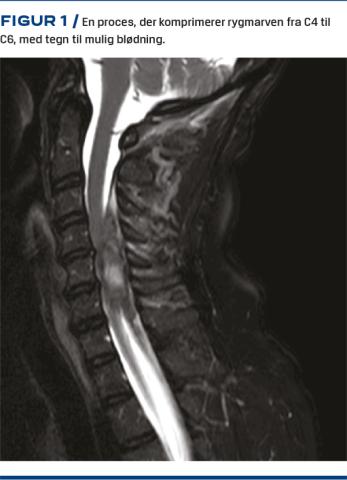

Der blev foretaget MR-skanning med kontrast af cerebrum og columna cervicalis, hvor man fandt en tumorlignende proces fra C4 til C6 på højre side i spinalkanalen (Figur 1). Processen målte 6,3 x 2,2 x 1,2 cm. Man påbegyndte behandling med prednisolon mod tumorødem. International normaliseret ratio var 3,4.